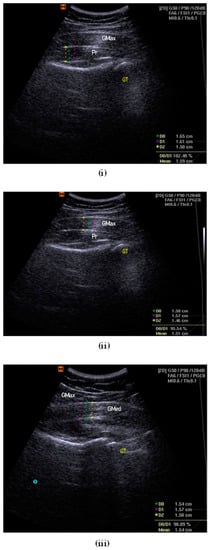

The participant was asked to perform an isometric contraction into a hip lateral rotation for several trials to assist with and confirm the identification of the piriformis muscle and fascial structures on the diagnostic USG viewscreen. The femoral greater trochanter was referred to as the main reference point, combined with the visual gliding of the piriformis muscle and the associated fasciae []. The depth and focus of the USG image were adjusted to portray the best possible image on the viewscreen. The thickness at the centre of the image was measured, considering the largest portion of muscle mass and excluding the surrounding fasciae that border the muscles []. The mean of three measurements of thickness was used for statistical analysis [] (Figure 1i).

Figure 1.

Examples of thickness measurement for piriformis (i), gluteus maximus (ii) and gluteus medius (iii). GT = greater trochanter of femur.

2.7.5. Gluteus Maximus Muscle Thickness

The participant was instructed to lie down in the prone position with both lower limbs at rest and in a neutral position. A curvilinear transducer was set at a frequency of 2.0–5.5 MHz to collect B-mode ultrasound images. During image acquisition, the transducer head was coated with a generous amount of ultrasound water-based transmission gel. The transducer was placed perpendicular to the skin and the lightest contact pressure was applied to ensure that the underlying tissues were not compressed. Measurement was taken at the first third, proximally 30%, between the PSIS and the greater trochanter of the femur []. The depth and zoom-in function were adjusted until the image of the sacrum could not be seen in the left third []. Once the best possible image was shown on the viewscreen, the image was frozen and the thickness of the gluteus maximus fibre was measured. The mean of the three measurements of thickness was used for statistical analysis [] (Figure 1ii).

2.7.6. Gluteus Medius Muscle Thickness

The participant was then instructed to lie on their side with the test leg up. The tested hip was placed in a neutral flexion/extension, neutral rotation, and at 20° of adduction (inclinometer confirmed) []. The tested knee was in full extension, with a Biofeedback® placed under the ankle and foot to ensure the resting position. A curvilinear transducer was set at 5.0 MHz (40-mm footprint; lateral and axial resolution of 1.0 and 0.93 mm, respectively) to collect bilateral anonymised resting B-mode ultrasound images []. Again, during image acquisition, the transducer head was coated with ultrasound water-based transmission gel and placed perpendicular to the skin. The lightest contact pressure was applied to ensure that the underlying tissues were not compressed. The transducer was placed midway between the proximal end of the iliac crest and the greater trochanter, approximately on the lower half of a coronal line located between the top of the greater trochanter and a point 25% of the distance between the ASIS and PSIS [,]. The cranial-caudal position of the transducer was adjusted until the superior lip of the acetabulum was one-third of the distance from the right border of the image []. The depth and zoom function were adjusted to obtain the best possible image before freezing. The thickness of the gluteus medius muscle was measured using callipers and it was considered as the distance between the inside edges of the muscle border, excluding the perimuscular fasciae. The mean of the three measurements of thickness was used for statistical analysis [] (Figure 1iii).